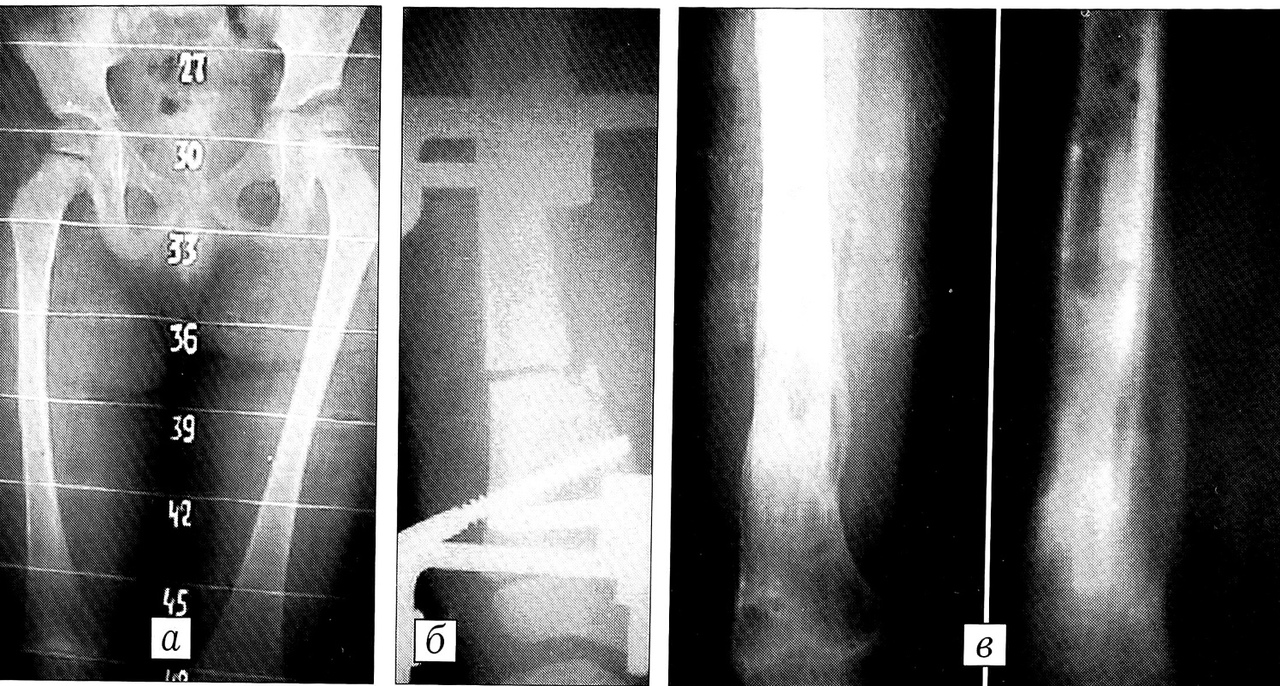

Больной М.,5 лет, диагноз: аномалия развития правой нижней конечности (класс 3), укорочение 23 см (рис. 1). На рентгенограммах: проксимальный отдел бедра отсутствует, бедро в порочном положении. На ангиограммах: единственная тонкая поверхностная бедренная артерия. С целью стабилизации конечности, выравнивания ее оси и обеспечения функционально наиболее выгодного протезирования произведена реконструктивная операция по Кингу — илиофеморальный артродез. Коленный сустав стал выполнять роль тазобедренного. Затем больному изготовлен ортопедический аппарат на правую нижнюю конечность.

Рис. 1. Больной М. 5 лет. Диагноз: аномалия развития правой нижней конечности (класс 3), укорочение 23 см. a — внешний вид при поступлении; б — отсутствие проксимального отдела бедра, отводяще-сгибательная контрактура; в — аплазия глубокой артерии бедра, гипоплазия бедренной артерии, отсутствие коллатералей; г — илиофеморальный артродез справа с фиксацией спицами (операция Кинга), коленный сустав на месте тазобедренного; д — через 3 мес после операции Кинга: больной в ортопедическом аппарате.